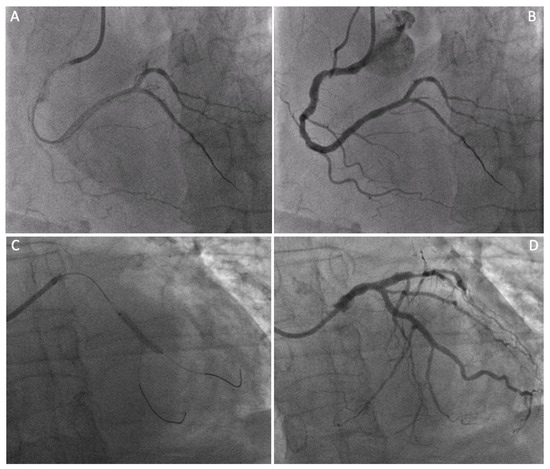

2.3. Preoperative Planning

2.4. Surgical Technique